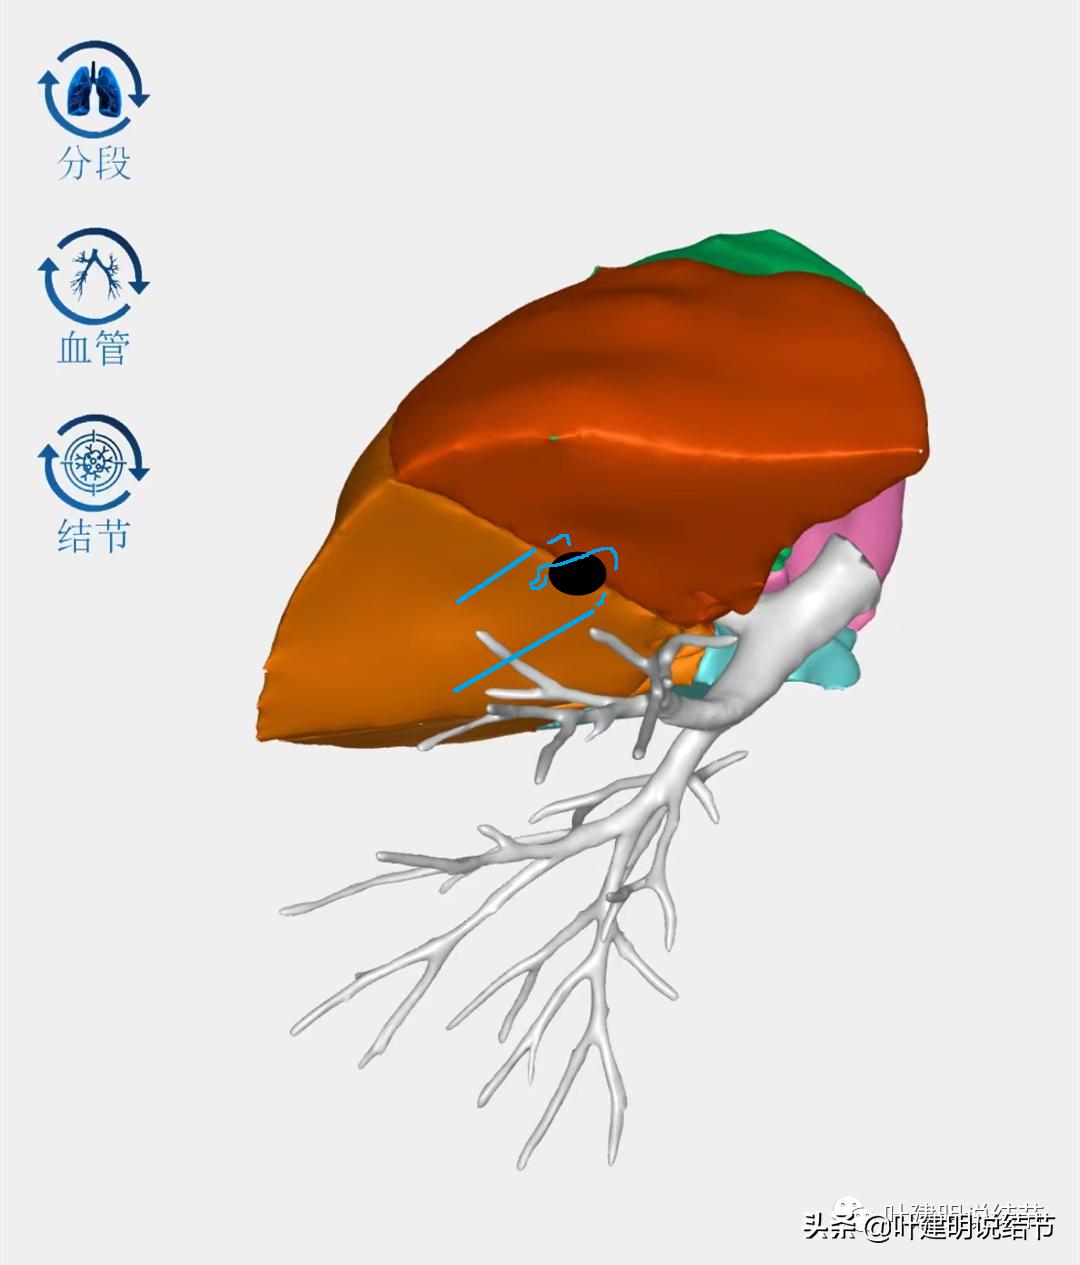

上叶病灶在三维视角上应该是类似上图的位置,它近水平裂,但窝在上叶凹向肺实质中央去的地方,其实术中是很难上钳去钳夹的,因为钉子是直的,即使切割缝合器能转弯,但钉匣仍是直的,距离肺门部又太近,病灶又凹在那里是有困难的。而如果我先在结节的边缘附近缝一针,将病灶提起来,是不是就能更容易卵圆钳夹并放置切割缝合器钉匣呢?如下图:

缝线后向下提,此处就被牵拉起来了,我们再在其基底部上钳并切割离断。这也是之前我建议其近期手术的原因之一。这样的操作只能针对小的结节,如果病灶再大,与肺门部距离再近,那就不能保证切缘足够。所以我之前在门诊与某A说,早点切可能能争取楔形,再进展后可能只能肺段切除,如果密度明显增加还可能要切肺叶。